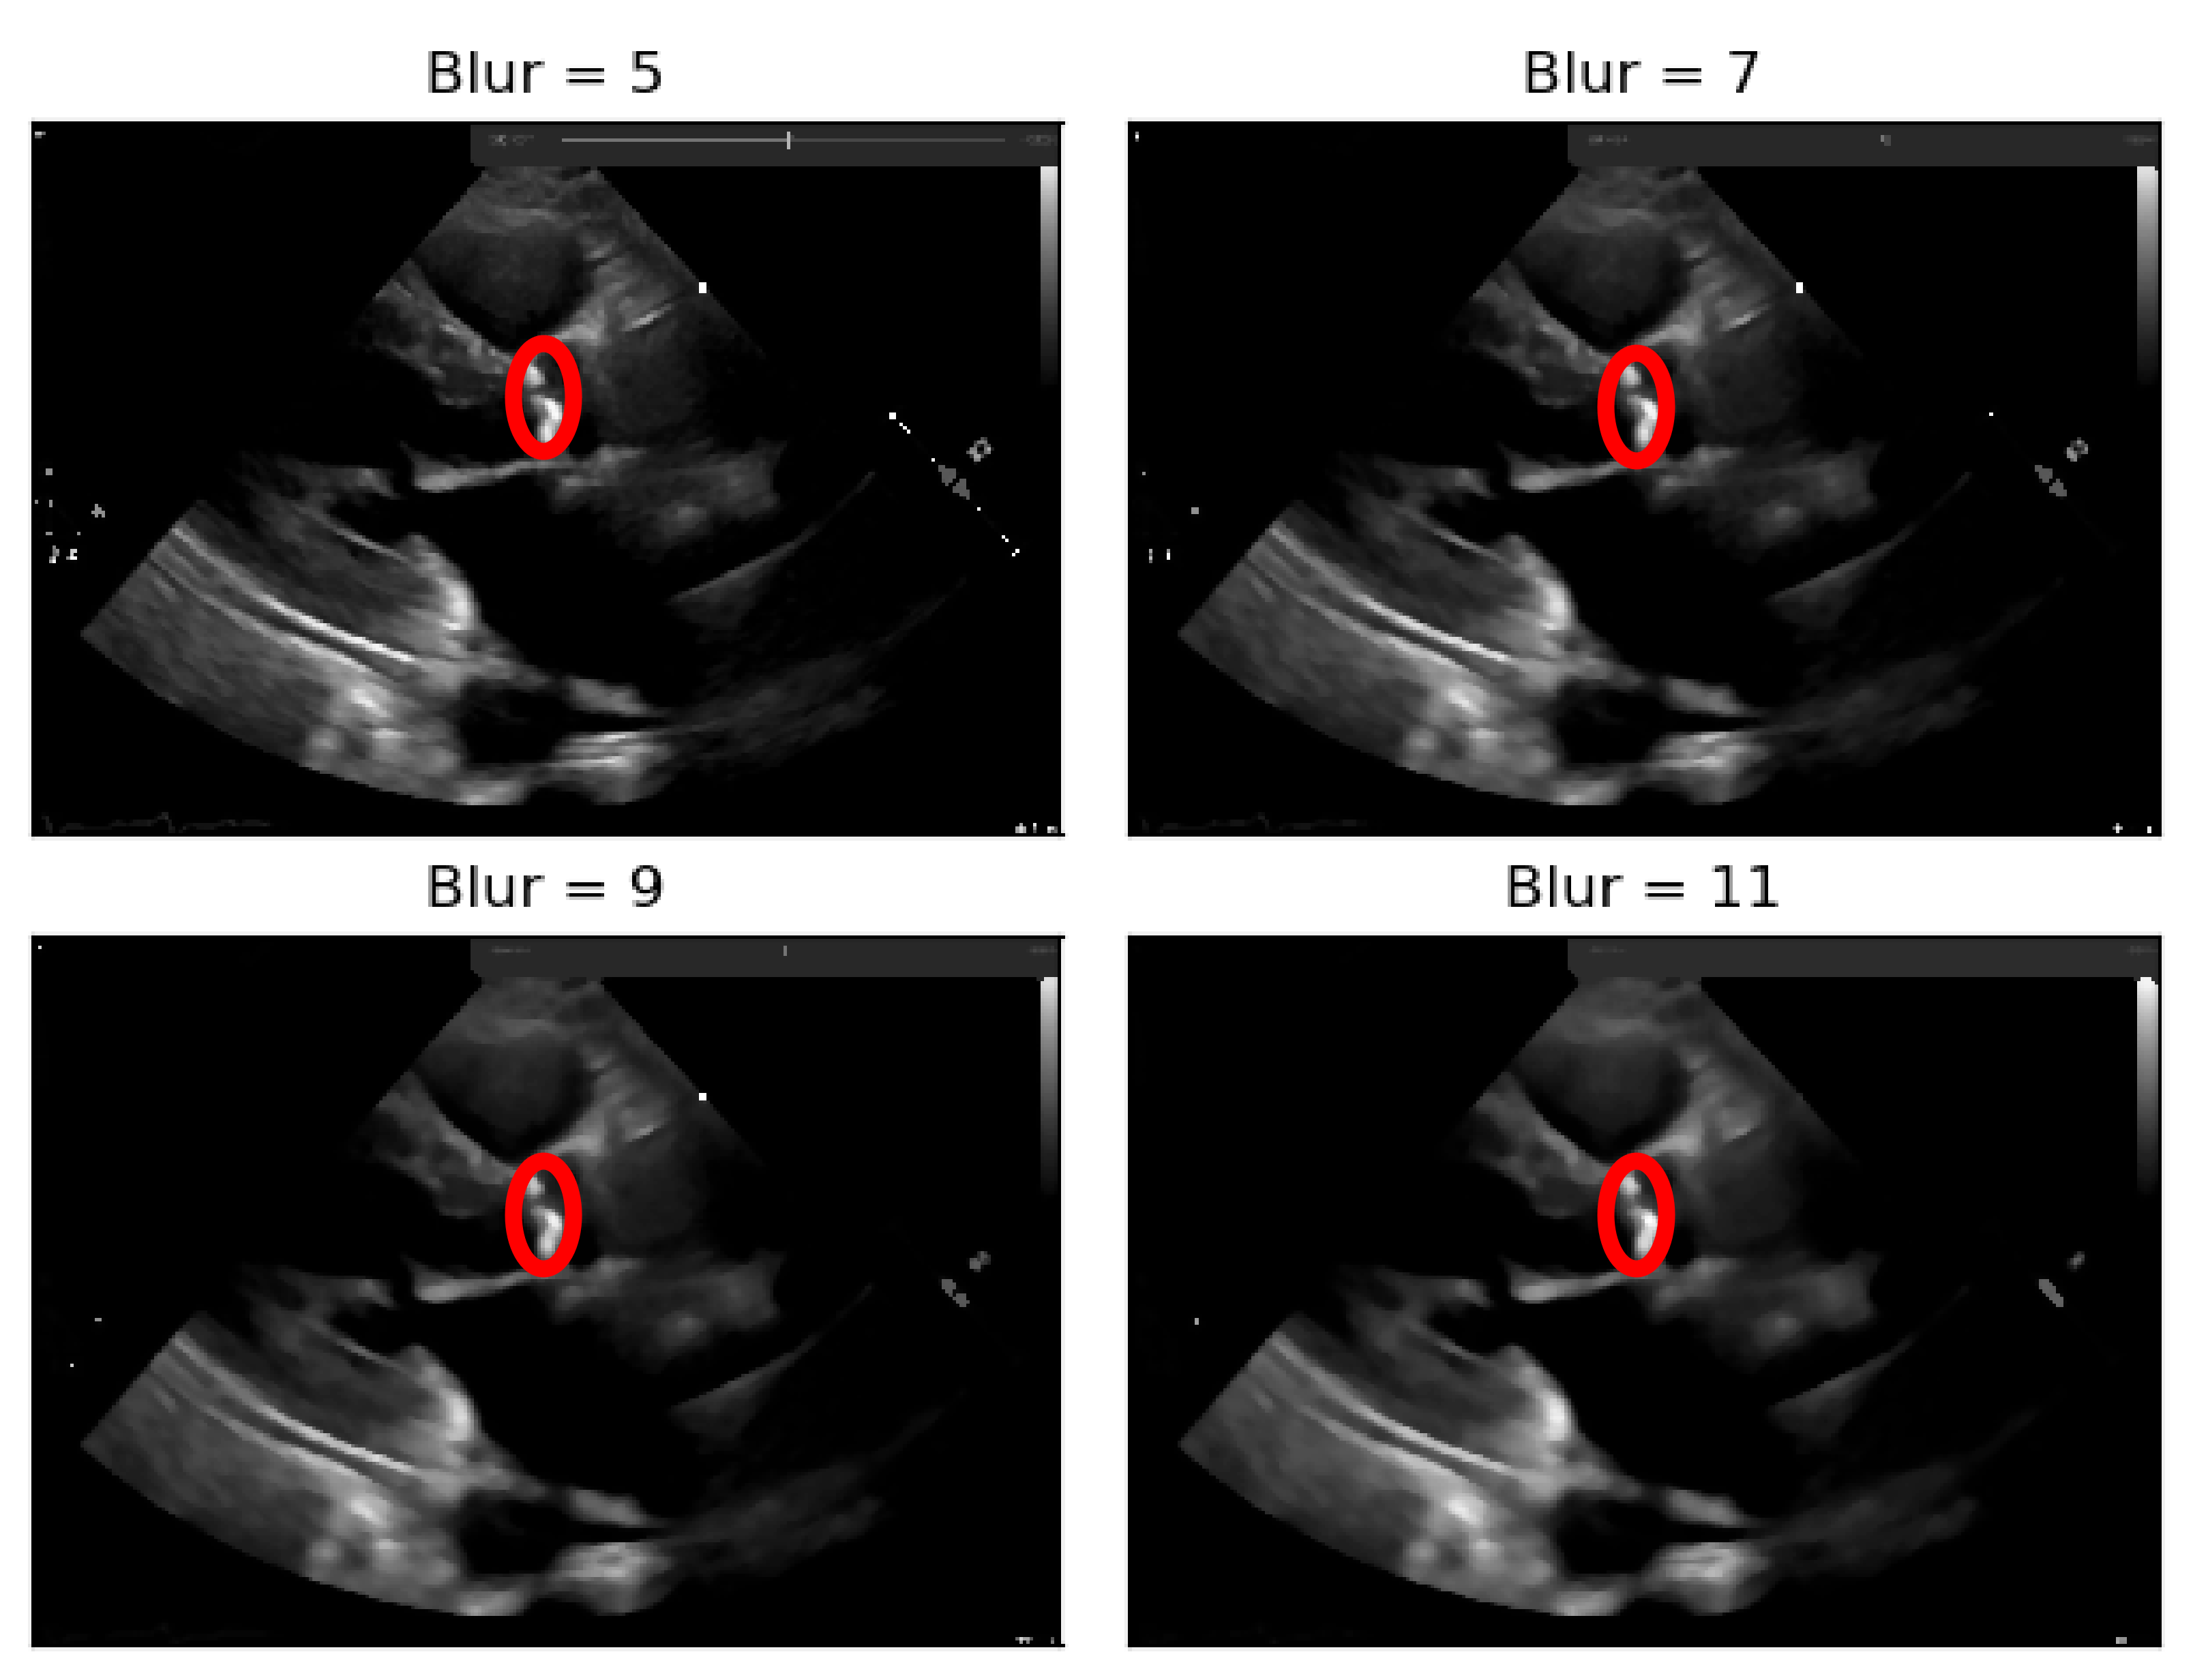

To deal with some natural constraints in terms of noise that characterize echocardiography imaging, particularly the process of sampling still images from the echocardiography video, different blurring treatments were performed to clean some of the image’s noise due to the echocardiography’s motion. Blurring an image will average rapid changes in the different pixel intensities, and this corresponds to a low-pass filter applied to the image [23], which removes noise while leaving the majority of the image structures still present in the image as depicted in Figure 4.

As it can be seen from Figure 4, when the Blur = 11 (experimentally adjusted with trial and error)), it can be easily identified, visually, in the regions where there is a presence of calcium (identified by the red circles). On this operation the central element of the image is replaced by the median of all the pixels in the kernel region, where the 11 means that it takes into consideration a kernel of 11 by 11.

Figure 4. Echocardiography image with four levels of blurring applied—the red circle represents our ROI where the aortic valve is located.